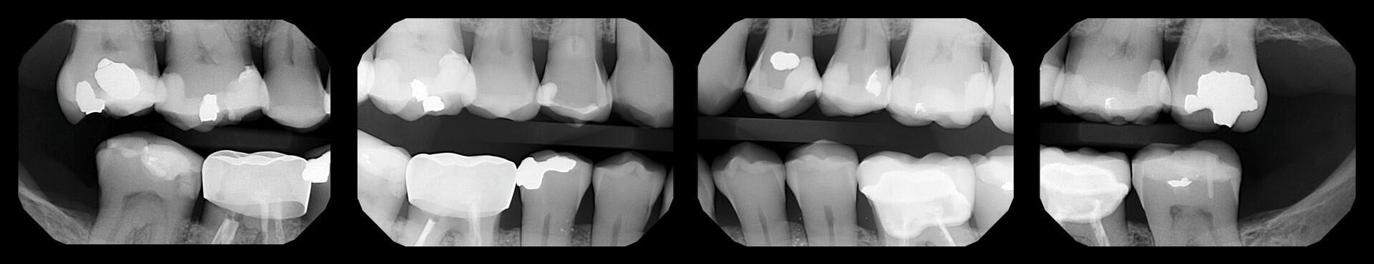

Fig 6. Preoperative bitewing imaging from general dentist.

Figure 6

A 52-year-old male patient was seen by his otolaryngologist for symptomatic and unilateral sinusitis of 6 months duration. Medical CT showed dental pathology (Figure 5). His general dentist had a bitewing radiograph on file and referred the patient for endodontic evaluation (Figure 6).

As part of the endodontic evaluation, CBCT imaging showed periapical pathology associated with tooth No. 14 as well as significant MSEO (Figure 7 and Figure 8). Clinical testing confirmed the absence of a cold response but no tenderness to percussion or palpation. A composite buildup was in place, absent evidence of recurrent decay. Soft tissues were unremarkable.

The diagnosis for tooth No. 14 was pulpal necrosis with asymptomatic apical periodontitis. NSRCT was completed (Figure 9), followed by full-coverage restorative care performed by the general dentist. A 3-month follow-up revealed resolution of prior sinus symptoms, normal clinical findings, and healing radiographic pathology, including periapical pathology and associated maxillary sinus mucositis (Figure 10 and Figure 11).